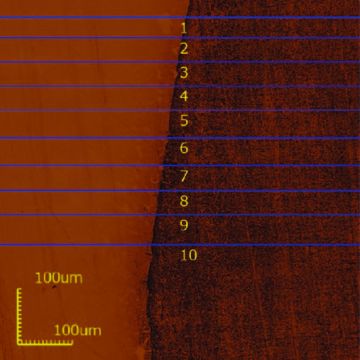

The use of a confocal laser microscope such as the Olympus LEXT OLS4000 leads to higher resolution as compared to a contact stylus as the microscope’s laser beam has a resolution of 0.4 μm. This is compatible with standard demineralization and does not cause damage on the sample surface because there are no contact forces between them (Figure 1).

Figure 1: Profilometry analysis of eroded dental enamel by hydrochloric acid.

Left side: corresponding control area. Right side: corresponding eroded area.